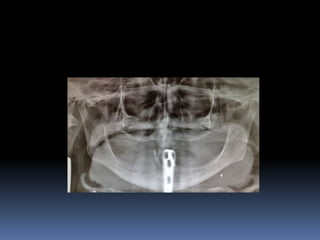

IMPLANTES ZIGOMÁTICOS     INDICAÇÕESMaxilar Edéntulo com Grande Reabsorção óssea		Pneumatização do Seio Maxilar	Status Pós-Maxilectomia	Fenda Lábio-Palatina

IMPLANTES ZIGOMÁTICOSFRACASSO FACIALHipoplasia maxilarFalso prognatismo